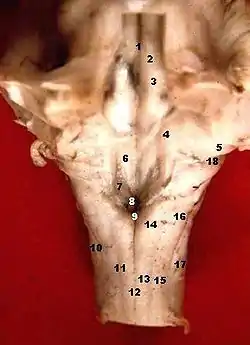

![]() Rhomboid fossa. | |

The rhomboid fossa is a rhombus-shaped depression that is the anterior part of the fourth ventricle. Its anterior wall, formed by the back of the pons and the medulla oblongata, constitutes the floor of the fourth ventricle.

It is covered by a thin layer of grey matter continuous with that of the spinal cord; superficial to this is a thin lamina of neuroglia which constitutes the ependyma of the ventricle and supports a layer of ciliated epithelium.

The fossa consists of three parts, superior, intermediate, and inferior:

- The superior part is triangular in shape and limited laterally by the superior cerebellar peduncle; its apex, directed upward, is continuous with the cerebral aqueduct; its base is represented by an imaginary line at the level of the upper ends of the superior foveae.

- The intermediate part extends from this level to that of the horizontal portions of the taeniae of the ventricle; it is narrow above where it is limited laterally by the middle peduncle, but widens below and is prolonged into the lateral recesses of the ventricle.

- The inferior part is triangular, and its downwardly directed apex, named the calamus scriptorius (as is shaped like a writing quill-nib)[1] is continuous with the central canal of the closed part of the medulla oblongata.

The sulcus limitans forms the lateral boundary of the medial eminence.

In the superior part of the rhomboid fossa it corresponds with the lateral limit of the fossa and presents a bluish-gray area, the locus coeruleus, which owes its color to an underlying patch of deeply pigmented nerve cells, termed the substantia ferruginea.

At the level of the facial colliculus the sulcus limitans widens into a flattened depression, the superior fovea, and in the inferior part of the fossa appears as a distinct dimple, the inferior fovea.

Lateral to the foveæ is a rounded elevation named the area acustica, which extends into the lateral recess and there forms a feebly marked swelling, the tuberculum acusticum.

Winding around the inferior peduncle and crossing the area acustica and the medial eminence are a number of white strands, the striæ medullares, which form a portion of the cochlear division of the acoustic nerve and disappear into the median sulcus.

Below the inferior fovea, and between the hypoglossal trigone and the lower part of the area acustica is a triangular dark field, the vagal trigone, which corresponds to the sensory nucleus of the vagus and glossopharyngeal nerves.

The lower end of the vagal trigone is crossed by a narrow translucent ridge, the funiculus separans, and between this funiculus and the gracile nucleus, is a small tongue-shaped area, the area postrema.

On section it is seen that the funiculus separans is formed by a strip of thickened ependyma, and the area postrema by loose, highly vascular, neuroglial tissue containing nerve cells of moderate size.